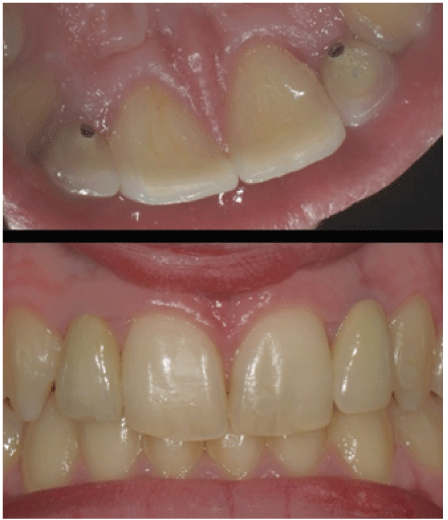

Figure 5: Two parallelized implants, applied with flapless technique. Downwards two immediate provisional elements at the end of surgery.

Figure 6: Two metal-ceramic crowns while being cemented. Downwards the same ones after two months.

Figure 8: 18 months Follow-up. The features of both parietal and vestibular mucosa can be seen. Healthy gingival tissue and good esthetic contours are present at the present follow-up.